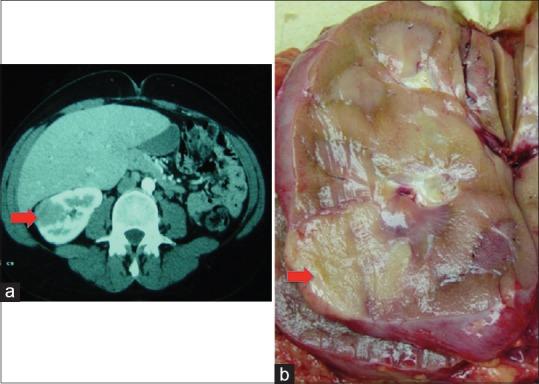

Sarcoidosis is a multisystem disease that commonly involves the lungs, but may also present with extrapulmonary manifestations. Genitourinary (GU) tract involvement has been traditionally thought to be rare, but that view may underestimate the true prevalence of the disease due to the often, silent presentation thereof.

There are a number of isolated case reports in the literature describing symptomatic and asymptomatic GU tract sarcoidosis. The world literature associated with the generalized syndrome was reviewed and summarized. Specific aspects of GU involvement are presented for each organ of the GU tract.

It is critical for the practicing clinician to have a working knowledge of the clinical manifestations of this disease as it involves the GU tract, as well as to be able to distinguish it from tuberculosis and the various malignancies that affect this organ system.